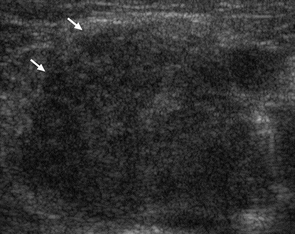

Some characteristics of malignant lymph nodes are eccentric hypertrophy, lack of an echogenic hilum, large size, cystic or necrotic areas, ill defined margins, and heterogenous appearance:

Normal lymph nodes, benign lymphadenopathy, and malignant lymphadenopathy all can mimic other structures on ultrasonography which is why the emergency physician should be aware of their appearance. Be aware of the anatomical distribution and location of lymph nodes to avoid misclassifying a lymph node as a blood vessel. Also obtain images in both longitudinal and transverse positions. Blood vessels will look very different in longitudinal and transverse positions however lymph nodes will retain their round appearance. If there is something that appears to be a fluid collection, search the surrounding area for other “fluid collections” as lymph nodes tend to appear in chains. Be aware that some fluid collections may contain separations and heterogenous material and can mimic lymph nodes. If in doubt, obtain a radiology based study.

Lymph node mimicking fluid collection:

Lymph node mimicking clot: